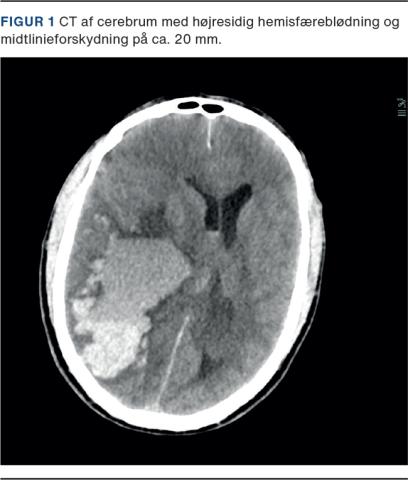

En 57-årig mand, som var tidligere rask og ikke fik medicin, blev indlagt efter fire dages anamnese med intens hovedpine. Ved ankomsten var patienten hypertensiv (med et blodtryk på 165/87 mmHg), bradykard (sinusrytme, frekvens 37 slag/min), ukontaktbar, Glascow coma score 6 med lysstive pupiller og anisokori. Blodprøver viste trombocytopeni (16 × 109/l), forhøjet fibrin D-dimer (> 20 FEU mg/l) og normal international normaliseret ratio (INR). Der blev foretaget en CT af cerebrum (CTc), som viste betydelig højresidig intracerebral hæmoragi (ICH) med midtlinjeforskydning (Figur 1). Der blev givet 2 g tranexamsyre intravenøst. Intubation og neuroprotektiv terapi initieredes med sedation (propofol/sufentanil), relaksans (rocuronium), hypertont saltvand (2 mmol/kg), eleveret hovedgærde og sikret middelarterietryk > 80 mmHg.